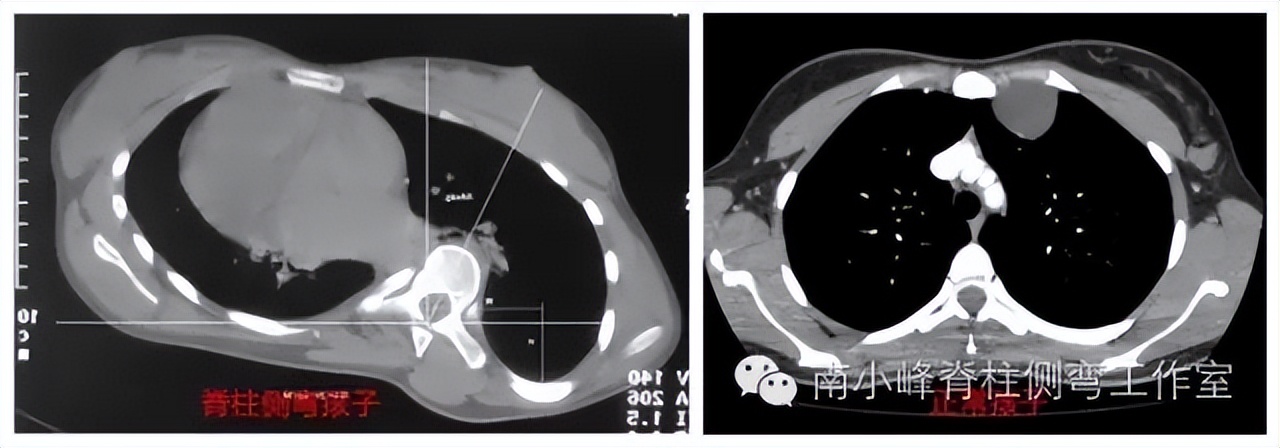

脊柱侧弯是脊柱在三维空间的畸形,各个椎体不但向侧方移动,同时还伴有旋转,如果胸椎侧弯较重时,附着在椎体上的肋骨也发生旋转和变形,如图1,我们通过CT在横截面扫描躯干,可以观察到,脊柱侧弯孩子肋骨的右后方和左前方突出,肋骨变形。背后引起“剃刀背”。前面导致乳房高低不一。右图为正常孩子的胸廓,两侧对称。